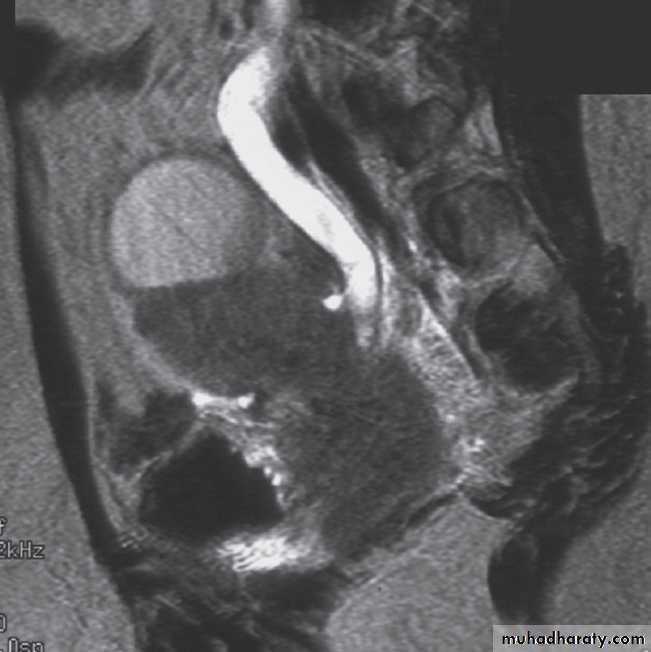

Magnetic resonance imaging

Magnetic resonance imaging gives similar anatomical information to CT, with the advantage of being able to obtain scans directly in multiple planes. It is generally used in selected circumstances , including :-To demonstrate renal artery stenosis .

- Inferior vena caval extension of renal tumours.

- To clarify problems not solved by ultrasound or CT.

-To assess the extent of bladder or prostate cancer prior to consideration for surgery.

Calcification is not visible on MRI, which is one of the main disadvantages of the technique for renal tract imaging.

Normal magnetic resonance imaging

As with CT and ultrasound, the renal contours should be smooth. Corticomedullary differentiation is best seen on T1-weighted images and immediately following intravenous contrast enhancement with gadolinium .The renal collecting systems, ureters and bladder are best seen on T2-weighted images, as the fluid returns a high signal intensity .

Some normal variants are well demonstrated on MRI:

-Fetal lobulation & a column of Bertin (which is normal renal parenchyma that may look mass-like) .Special techniques